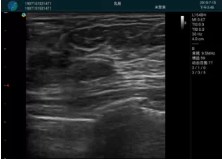

可視化穿刺引導(dǎo)

M20實(shí)時(shí)引導(dǎo):向包塊后方間隙注射利多卡因

清晰顯示腺體內(nèi)低回聲快影,邊界清晰,包膜較光滑

確定進(jìn)針路徑并實(shí)時(shí)監(jiān)測抽吸針與腫塊位置關(guān)系

抽吸針進(jìn)入腫塊內(nèi)部進(jìn)行旋切

抽吸過程中可見腫塊明顯縮小,并根據(jù)腫塊位置改變針道位置

抽吸旋切后再進(jìn)行超聲復(fù)查,原腫塊區(qū)域未見殘留組織及出血